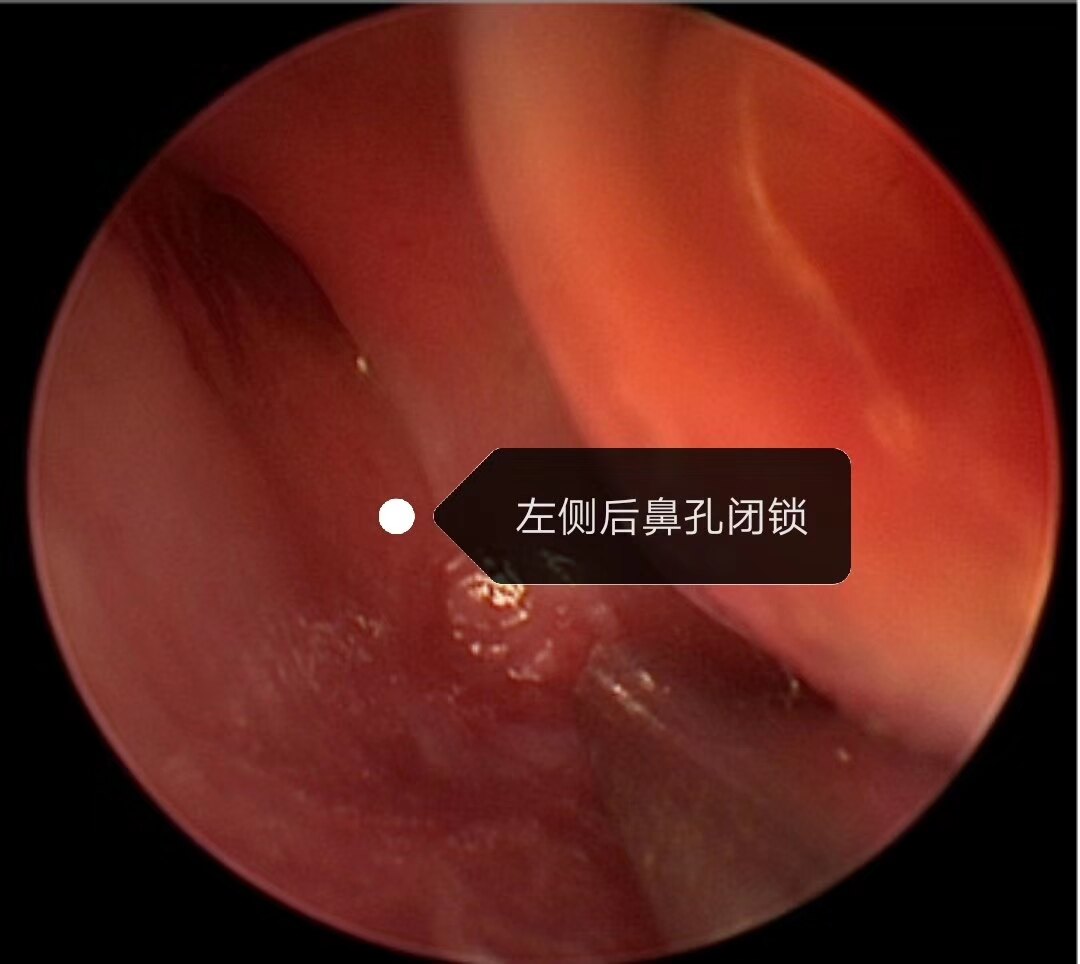

先天性后鼻孔闭锁 新生儿双侧先天性后鼻孔闭锁,表现为呼吸困难,吃奶时明显,哭闹后可暂时缓解

先天性后鼻孔闭锁是一先天性发育畸形,分单侧闭锁和双侧闭锁,双侧后鼻孔闭锁会出现周期性呼吸暂停和窒息,危及患儿的生命安全和影响鼻腔颌面部的发育,需要及时手术治疗。术后造孔容易出现再次闭锁和狭窄,常需多次手术干预,是医生和患儿家庭面临的难题。